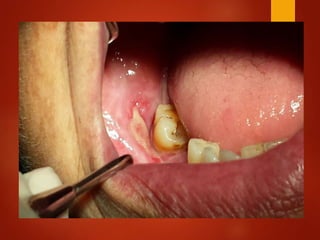

El documento es un registro médico odontológico que muestra las fechas de las visitas de un paciente al centro de salud El Raval, incluyendo exámenes y tratamientos realizados como la extracción de cálculos salivales en abril y mayo de 2012.